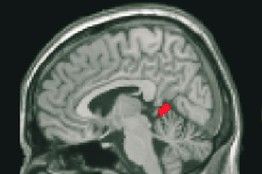

圖:研究人員發現,隨著大腦內與語言技能有關的區域發生改變,語言智商也會相應地發生巨大的改變,而非語言智商是隨著與手部動作的相關一個區域變化而變化的。

為了更好地理解智力,普賴斯和她的同事研究了33位健康的英國青少年,這些人的智商最初在80──140之間。他們在2004年對這批志愿者進行了標準化智力測試,在2008年又進行了一次測試,以此來涵蓋這些人青春期的高峰年份。研究人員用機能性磁共振成像儀來監測這批青少年大腦結構的細微變化。通過分別分析受測者的語言智商成績和非語言智商成績,研究人員發現,這些基本智力方面可能會發生明顯變化。